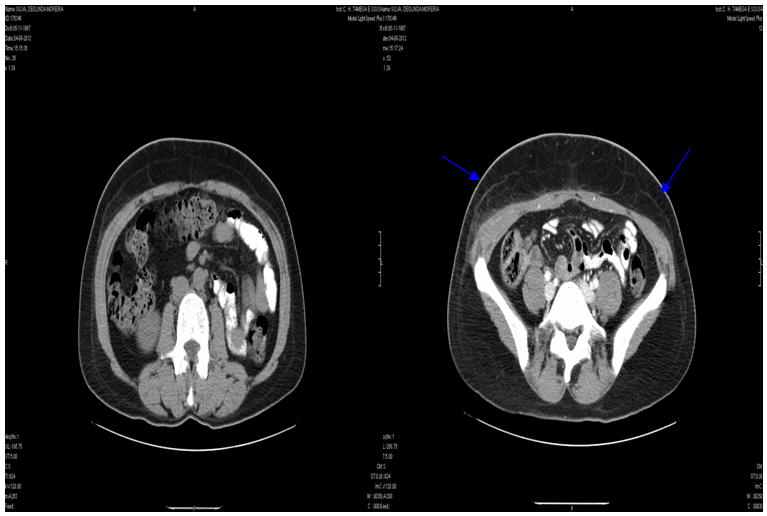

On the sixth day after surgery, the patient was admitted to the emergency room (ER) with right low back pain with anterior irradiation and hyperthermia. At ER the patient presented with axillary temperature of 38.2oC, hemodynamic stability, and slightly colorless but hydrated mucous. Abdomen was soft but very painful at palpation on the right flank without peritoneal signs. An ecchymosis with 5 cm was observed on the right low back area. The surgical scar was reddish, without any inflammatory signs. The gynecologic exam was normal. A renal ultrasound was performed and it only showed a thickening of the right lateral abdominal wall. A abdominal computerized tomography (CT) scan was performed to clarify the thickening, and it revealed thickening of the right oblique muscle with 95x35mm, suggesting oblique muscle hematoma, without any signs of active hemorrhage (Figure 1). Blood count revealed hemoglobin 9.6g/dl, leucocytes 11.900 with 87% neutrophils, CRP 338, and normal renal function. The microbiologic urine test made on the 3rd day after surgery isolated an E. Coli resistant to amoxicillin and clavulanic acid. Reexamination of the patient revealed a subcutaneous hardening at the site of the ecchymosis that was extremely painful at palpation, she denyabdominal trauma.

Figure 1 Computerized tomography shows a oblique of right oblique muscle and asymmetric thickening of the oblique muscles (blues arrows).